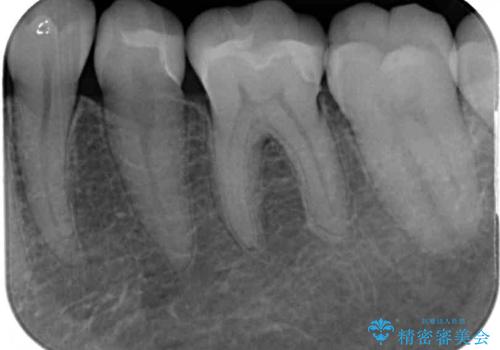

そして次の来院時、セラミックインレーを装着し、噛み合わせなどの調整を行います。

自然な色調で大変満足されました。